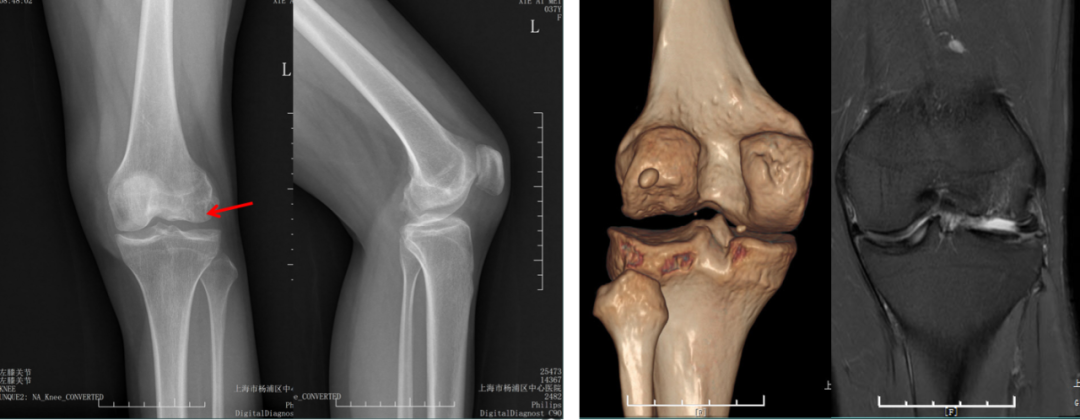

股骨后髁过截

外侧股骨髁坏死伴发育不良。

股骨假体过屈

外侧单髁术后股骨后髁过截,股骨假体过屈(45°)。